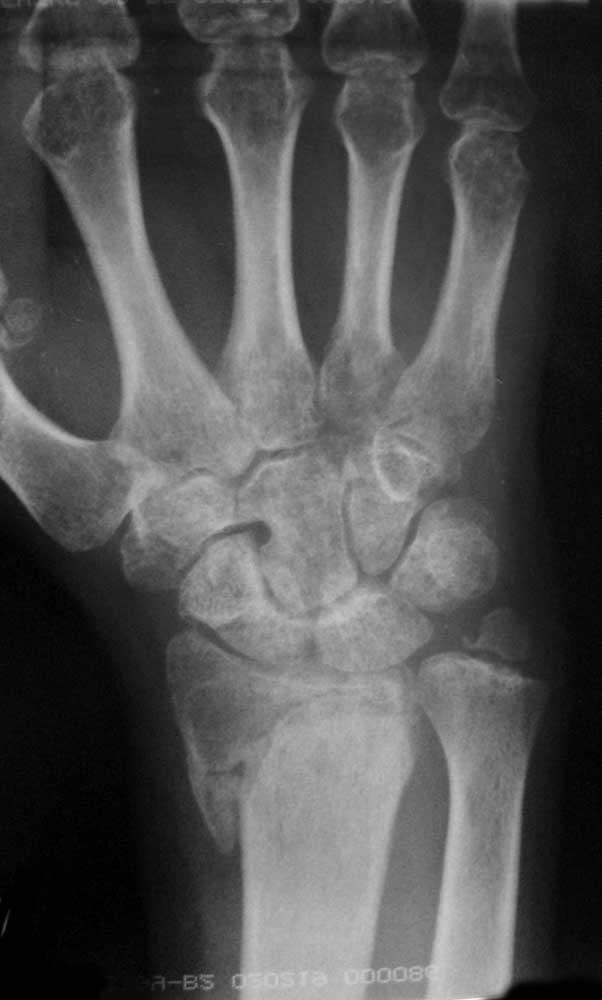

Пациент,39 лет, 02.08.2009 кататравма, падение с 5 этажа. Перелом дистального метаэпифиза лучевой кости, шиловидного отростка локтевой кости правого предплечья, перелом дистального метаэпифиза лучевой кости левого предплечья.

Лечился в Ставропольском крае. Слева - иммобилизация в течение месяца, в настоящий момент не беспокоит, функцией доволен. Справа - контрольные снимки 15.08.2009, закрытая ручная репозиция, иммобилизация в положении ладонного сгибания. 02.10.2009 контрольные рентгенограммы (приведены ниже), травматологом заподозрено формирование ложного сустава, направлен на стац.лечение, смена лонгеты на прямую. Иммобилизация до настоящего времени. Беспокоят боли в области кистевого сустава, точка максимальной болезненности в проекции шиловидного отростка локтевой кости.

Объективно: движения в кистевом суставе ограничены, ладонное сгибание 30 градусов, активные тыльное сгибание, лучевое, локтевое отведение отсутствуют, попытки пассивных движений болезненны. Патологической подвижности не определяется.